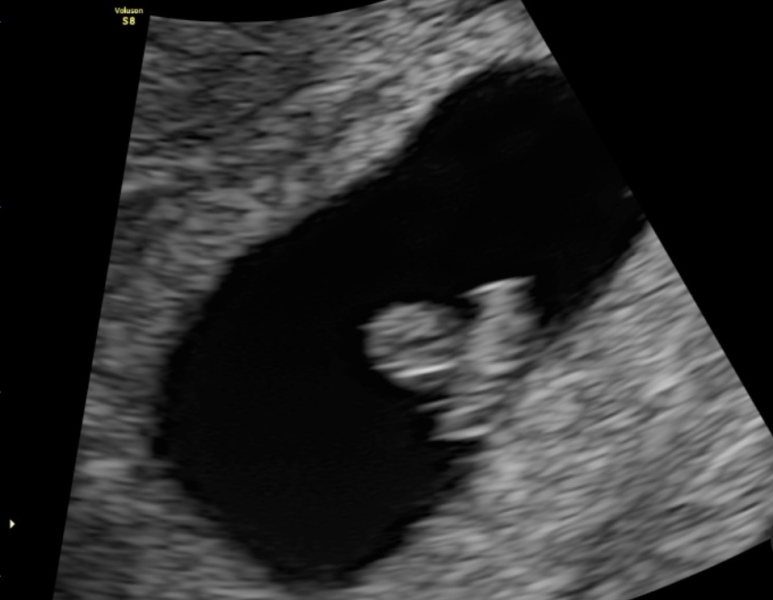

DiamondApricot · 04/04/2023 18:11

I've got pics but there isn't a huge amount to see, the circle at the top is the yolk sac.